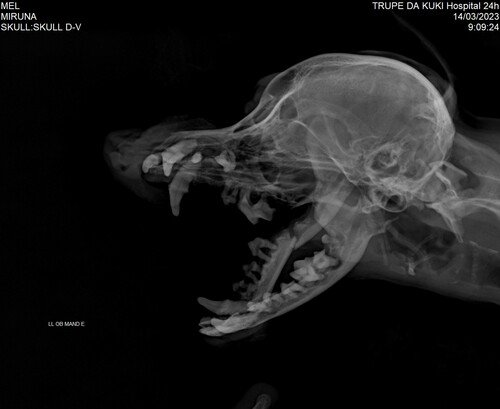

Sou a Mel, tenho 9 aninhos e sou uma podlee. Fui adotada pela mamãe Miruna e pela vovó Inês há 3 anos. Sou muuuuito amada e feliz, e sei que faço elas felizes também. Mamãe e vovó ficam impressionadas com a minha inteligência e como eu falo só com o olhar. Mas, dia 10/03 fui atacada por outra cachorrinha. Vou precisar fazer uma cirurgia para colocar prótese na minha mandíbula que foi quebrada por conta do ataque. Até agora foram R$ 3.000,00 entre internação, exames e cirurgia. Os gastos vão aumentando com o passar dos dias internada (tem um valor em aberto que minha mamãe ainda não sabe exatamente) e mais cirurgia na mandíbula com internação e anestesia vai dar em torno de R$ 2.500,00. Minha família não tem como arcar com todos esses custos que surgiram de repente. Sou muito importante para minha família, pois assim como recebo muito amor, também dou muito amor, sou companheira, alegro e trago luz para mamãe e vovó e todooos que me conhecem. Por isso, eu e minha família pedimos a ajuda de vocês para que eu não tenha mais dores e tenha uma mandíbula novinha, assim posso voltar logo pra casa! Aubrigada.